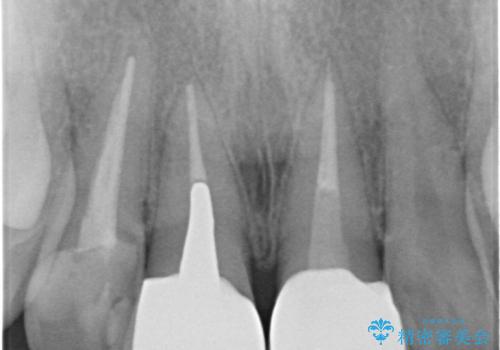

- 前歯のバランスが悪いとの事で来院。

左の前歯は樹脂での治療がされていてう蝕が再発していたので全て取り除き、再根管治療(保険)を行いました。

右の前歯も被せ物を外して左右一緒に作製した方が同じ色で作れるので被せ物のやりかえを行いました。(再根管治療は望まなかった)